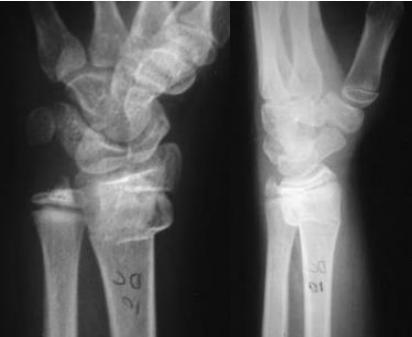

Injured and uninjured wrists after premature physeal closure

Asymmetrical Physeal Affection

- Seen on x-ray

- One side grows more than the other

- Causing an increasing deformity

- Oblique Park-Harris growth arrest/recovery line (white arrows)